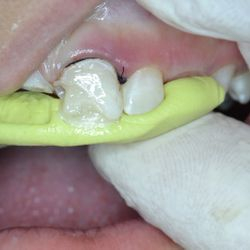

Αποκατάσταση Κατάγματος Οπισθίου Δοντιού

Ο ασθενής προσήλθε στο ιατρείο με κάταγμα του υπερώιου φύματος του άνω δευτέρου προγομφίου.

Αφαιρέθηκε η παλιά έμφραξη αμαλγάματος και προετοιμάστηκε κατάλληλα το δόντι.

Έγινε νέα έμφραξη νανο-υβριδικής σύνθετης ρητίνης τελευταίας γενιάς (HerculiteXRVUltra/Kerr) και το δόντι απέκτησε ξανά το σχήμα και την αντοχή που είχε πριν σπάσει.